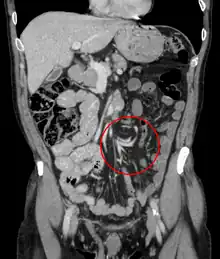

| Coronal CT of the abdomen, demonstrating a volvulus as indicated by twisting of the bowel stock | |